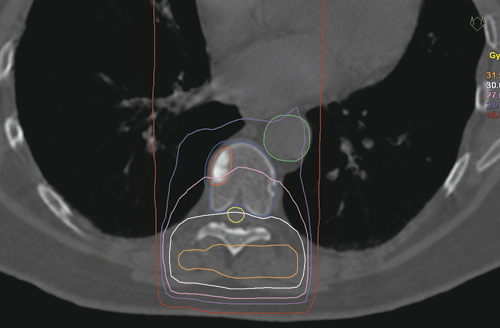

Konvensjonell strålebehandling med et enkelt feltoppsett innebærer en lite ressurskrevende planleggingsprosess og er et veletablert behandlingstilbud for disse pasientene. Man gir vanligvis ti daglige behandlinger à 3 gray (Gy), eller sjeldnere en engangsbehandling med 8 Gy, og hele stråledosen gis inn rett bakfra. Siden medulla spinalis dermed uvegerlig blir liggende inne i det bestrålte området, må behandlingsdosen legges under den optimale terapeutiske dosen for å unngå overdosering til medulla (fig 1). Ryggmargen er et strålefølsomt organ, og for høye doser til denne kan i verste fall føre til lammelser. Muligheten for varig lokal tumorkontroll er derfor relativt liten (4)-(6). Dersom en tidligere bestrålt ryggradsmetastase øker i størrelse eller det oppstår metastaser i nabovirvler, kan konvensjonelle fraksjoneringer og behandlingsopplegg også være problematiske, siden effekten av tidligere strålebelastning på medulla i liten grad er reparert.

Vi tilbyr nå behandling hvor den beregnede dosefordelingen er ekvivalent med høyavansert stereotaktisk behandling, mens planleggingsfasen er sammenliknbar med de enkle konvensjonelle metodene når det gjelder ressursbruk. Et vesentlig moment er at den beregnede dosen til medulla må holdes på et minimum, mens dosen til virvelen som behandles må være høy nok til å gi varig lokal effekt. Løsningen ble å lage et templatbasert behandlingsopplegg, altså et opplegg som i utgangspunktet er uavhengig av den enkelte pasient, men som med små justeringer kan tilpasses pasienten. Behandlingen gis med ni standardiserte feltvinkler, som gjør at strålingsdosen blir fordelt utenom medulla (fig 2). Resultatet ble en planleggingsprosess som i de fleste tilfeller tar 15 – 30 minutter, mens de mest vanlige planleggingsprotokollene ville krevd flere timer.

Den beregnede dosefordelingen gir betydelig høyere svulstdose, og en tilfredsstillende skjerming av risikoorganene i nærheten av behandlingsområdet, sett i forhold til konvensjonell behandling. Tumorområdet får over 18 Gy (midlere strålingsdose 24 Gy), mens medulla får maksimalt 12 Gy. Til sammenlikning er dosefordelingen fra et tradisjonelt opplegg, der 30 Gy gis i ti fraksjoner, vist i figur 1.